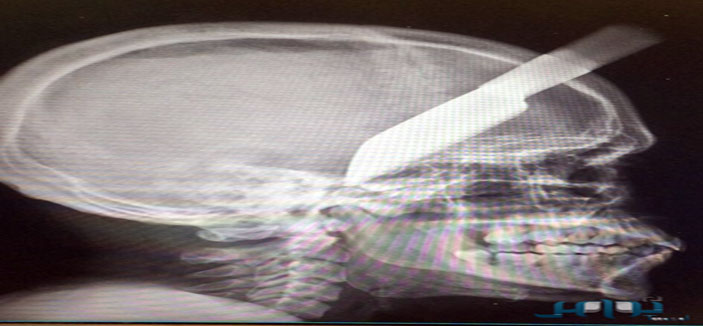

مكة المكرمة: سكين يستقر في رأس شاب .. وفريق جراحي ينقذه

مكة المكرمة - سامي علي: تمكن نجاح فريق طبي من مستشفى النور التخصصي بمكة المكرمة بفضل من الله